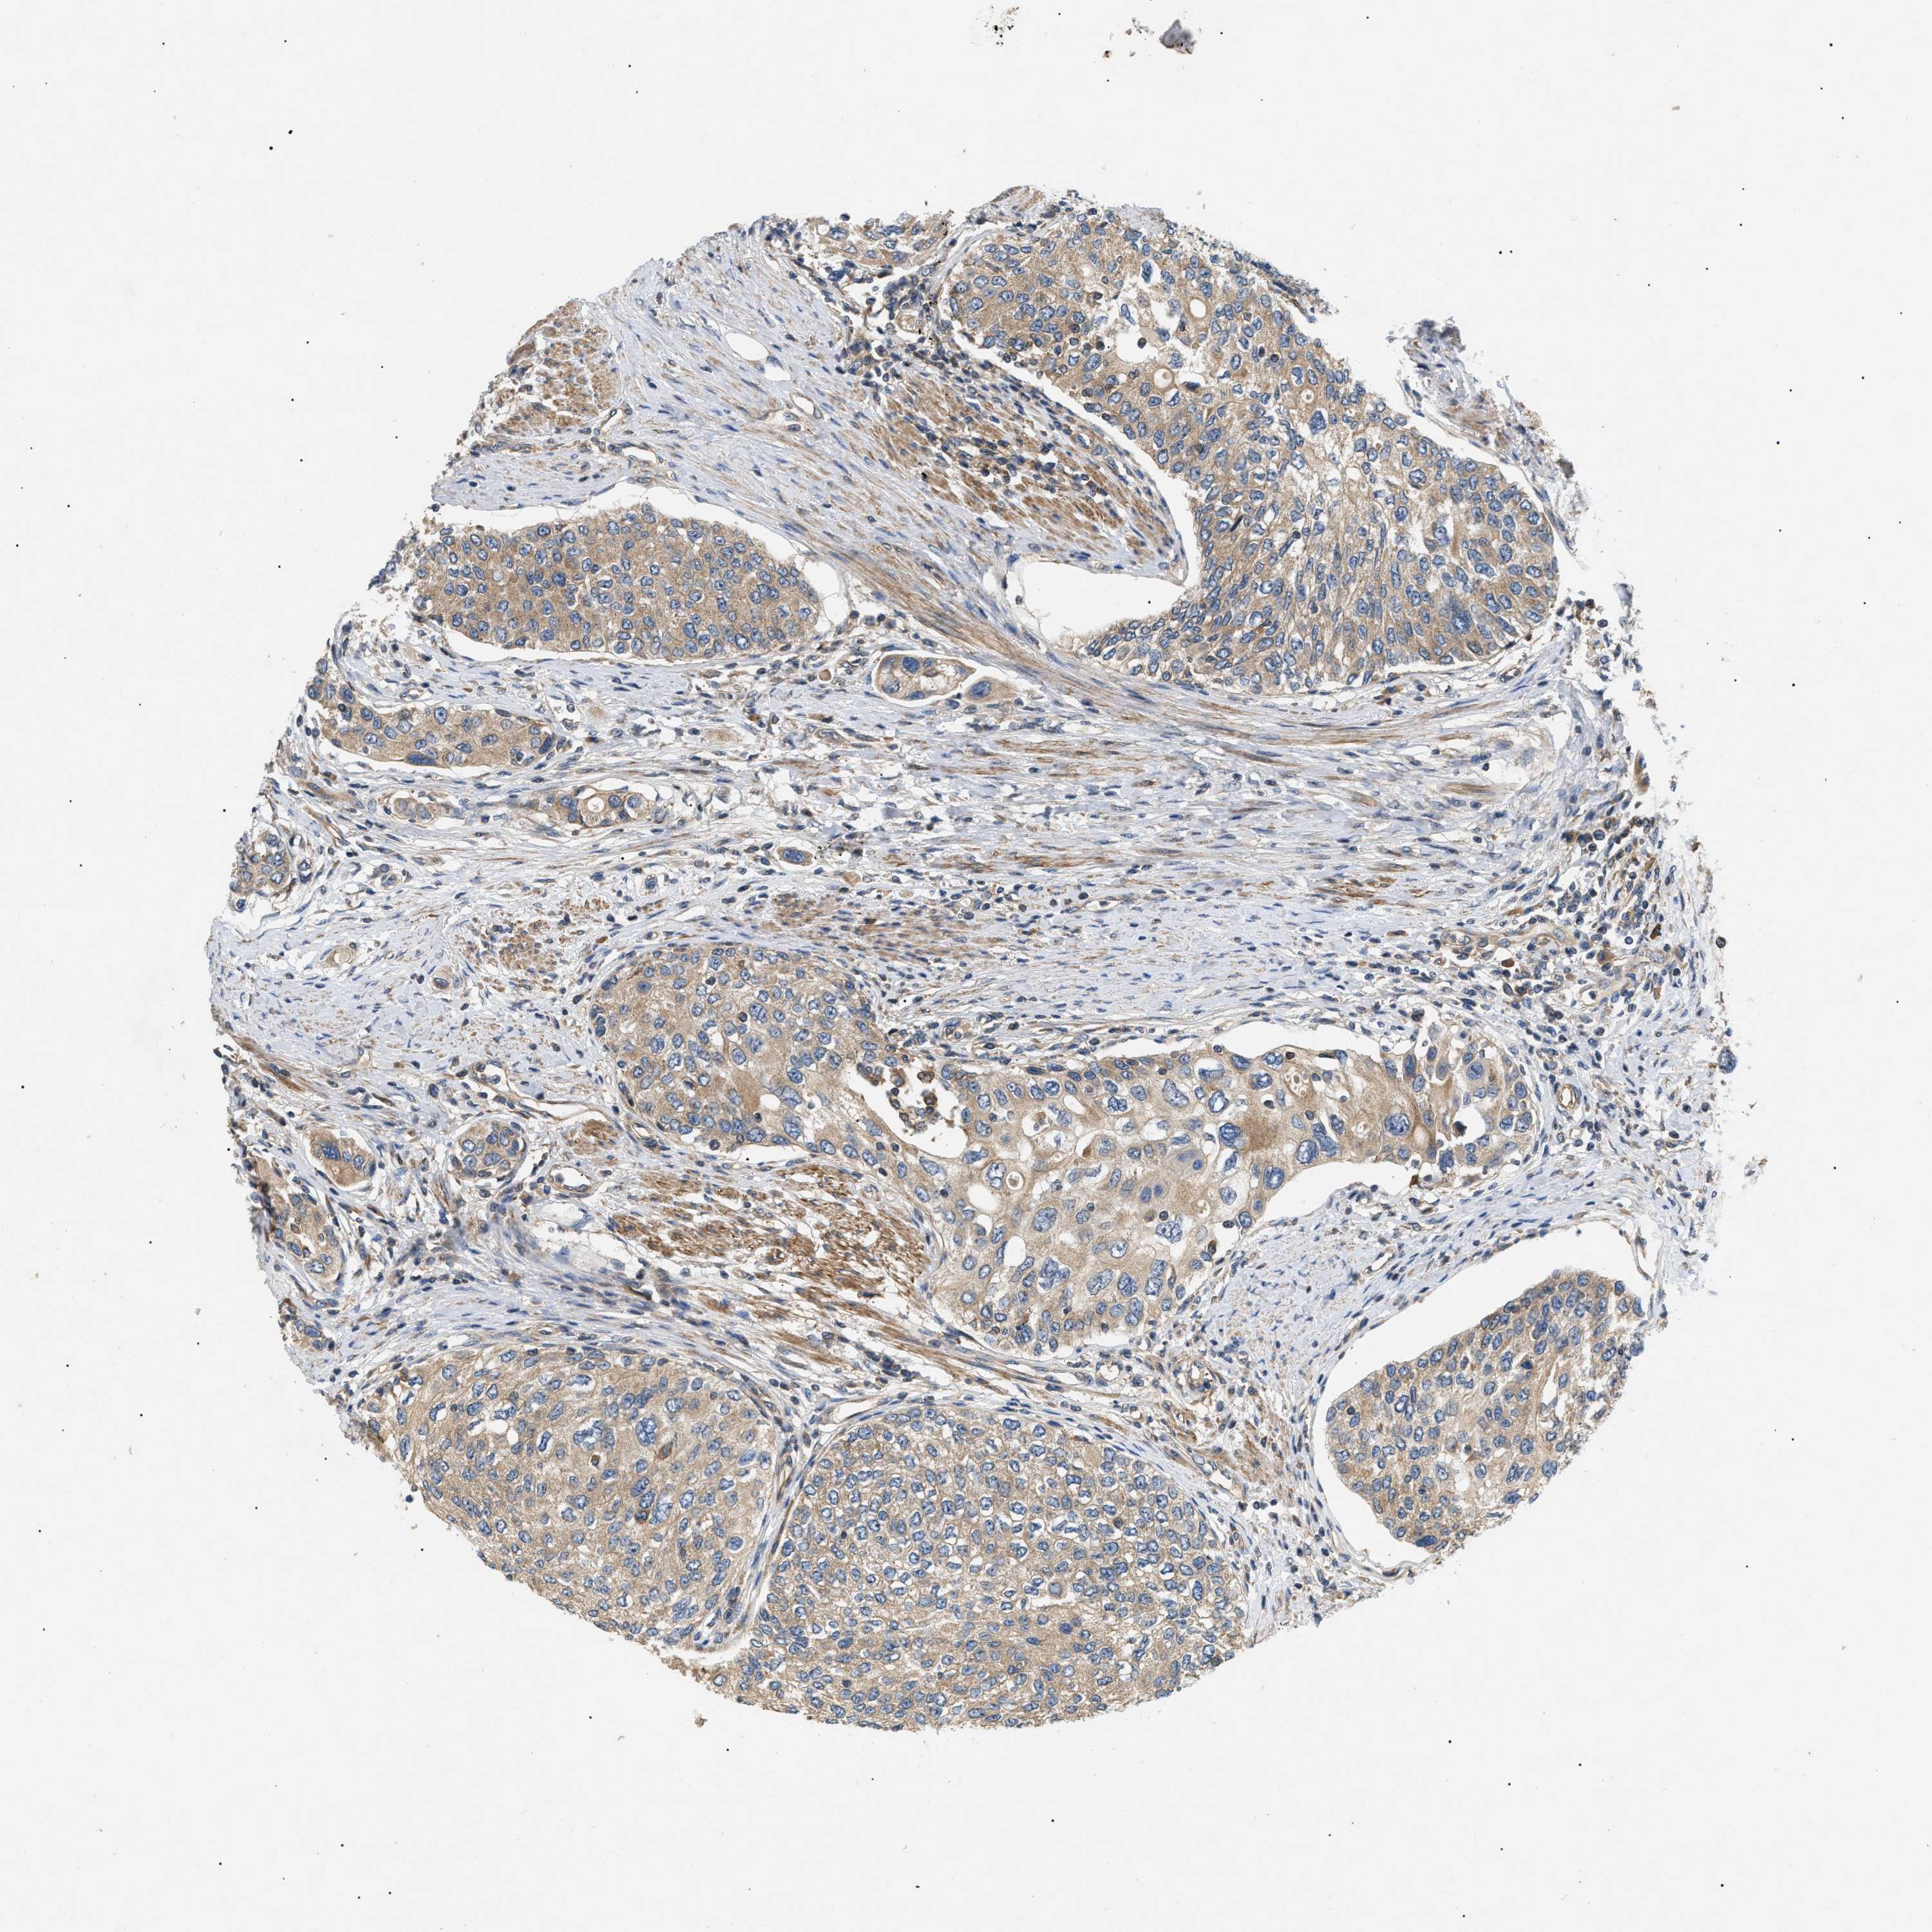

UROTHELIAL CANCER - Protein expressioni

A mouse-over function shows sample information and annotation data. Click on an image to view it in a full screen mode. Samples can be filtered based on level of antibody staining by selecting one or several of the following categories: high, medium, low and not detected. The assay and annotation is described here.

Note that samples used for immunohistochemistry by the Human Protein Atlas do not correspond to samples in the TCGA dataset.

Antibody stainingi

Antibody staining in the annotated cell types in the current human tissue is reported as not detected, low, medium, or high, based on conventional immunohistochemistry profiling in selected tissues. This score is based on the combination of the staining intensity and fraction of stained cells.

Each image is clickable and will lead to virtual microscopy that enables deeper exploration of all samples and also displays staining intensity scores, fraction scores and subcellular localization as well as patient and tissue information for each sample.

Antibody HPA016745

Staining

High

Medium

Low

Not detected

Intensity

Strong

Moderate

Weak

Negative

Quantity

>75%

75%-25%

<25%

None

Location

Nuclear

Cytoplasmic/membranous

Cytoplasmic/membranous,nuclear

Urothelial carcinoma, Low grade

Urothelial carcinoma, High grade